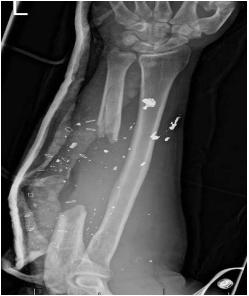

Figure 2: An X-ray of the traumatic limb illustrating a large segment of missing ulna with stable wrist and elbow joints.